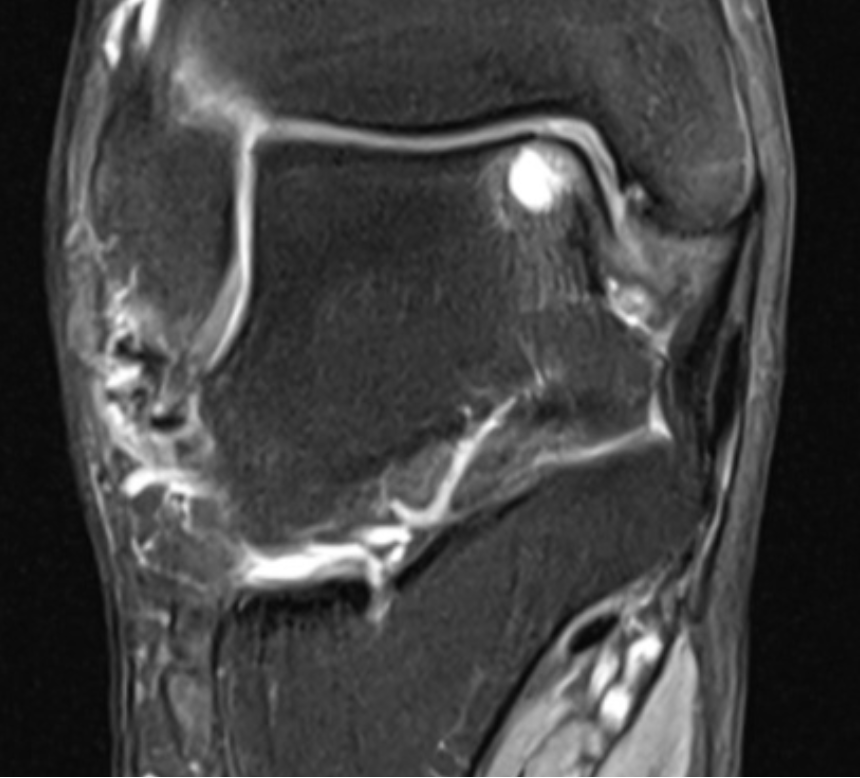

- The surgery involves looking inside the ankle with a camera (see Ankle Arthroscopy) and identifying the osteochondral defect (OCD).